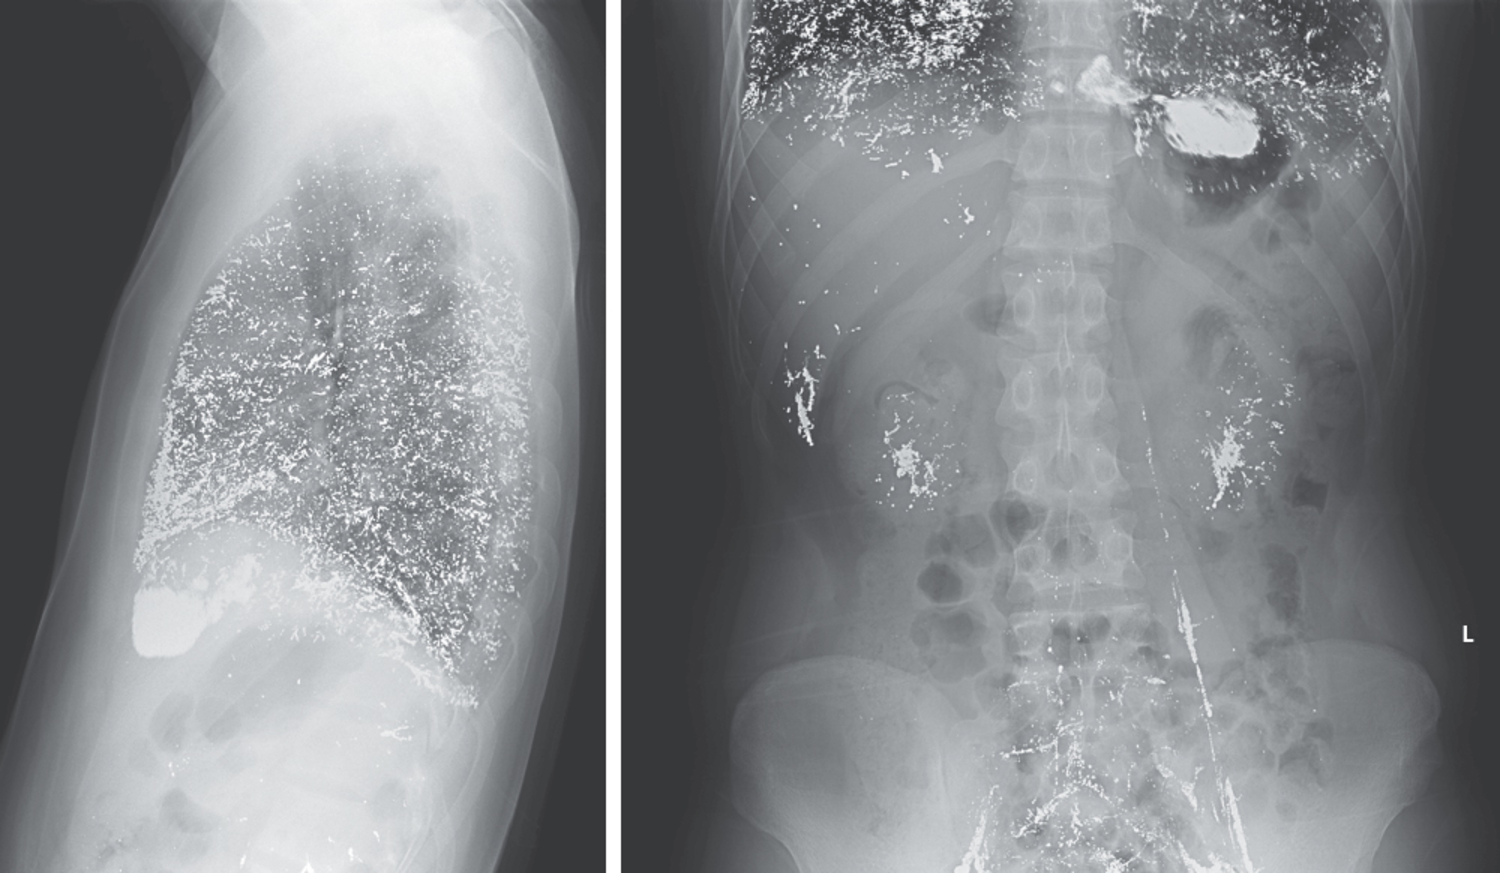

25-летний мужчина обратился в клинику общей медицины с 3-месячной историей повышенной утомляемости, тошноты и сухого кашля. Лабораторные исследования показали уровень гемоглобина 6,5 г на децилитр (референсный диапазон от 12,0 до 16,0) и нормальную функцию почек. Были получены ...